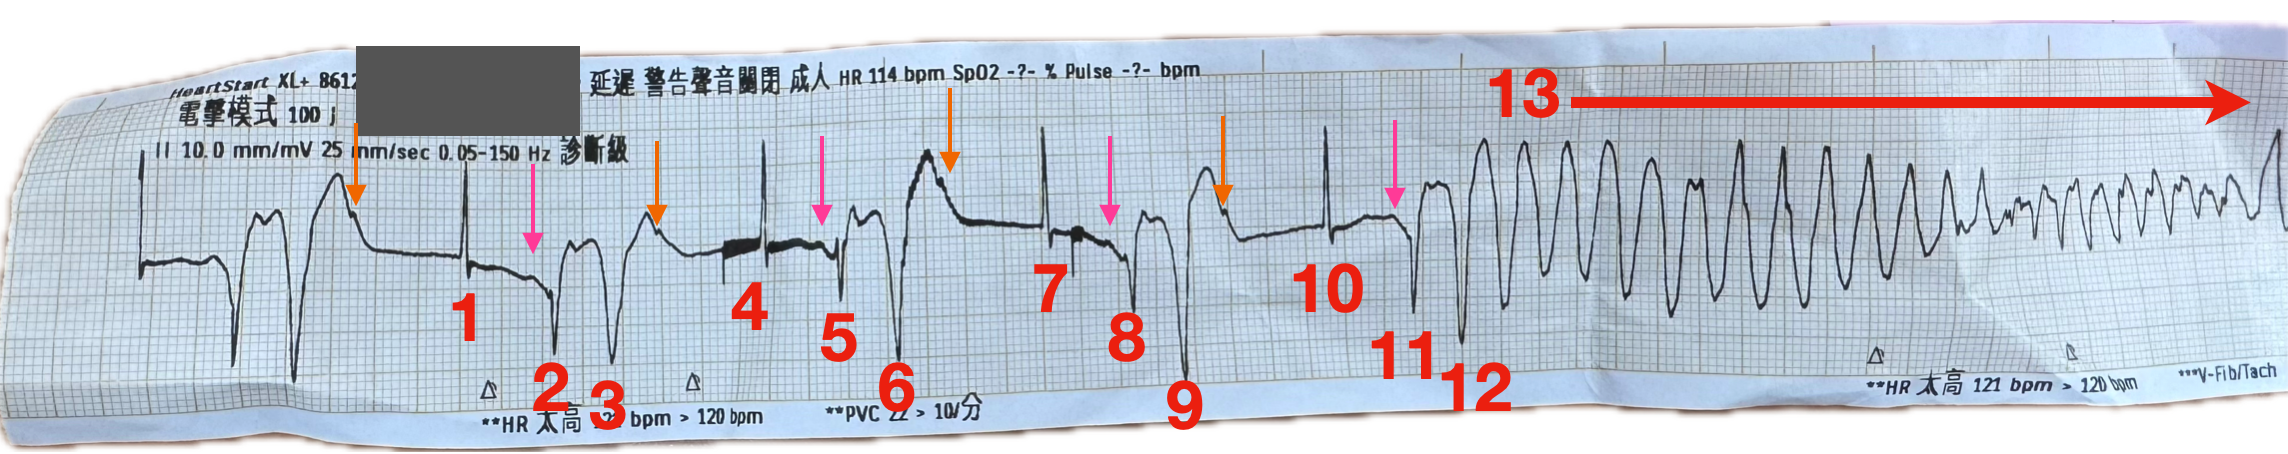

讓我們來分析這張ECG strip,我把Fig.6稍微標示了一下

仔細看,這rhythm其實亂中有序。

123、456、789、101112都各為一組

1、4、7、10都是同一個beat

- 具有narrow QRS、但是沒有看到明顯P wave,還是前面橘色箭頭的是這個beat的P wave嗎?

2、5、8、11都是同一個beat

- 這個beat,和前一個beat很明顯不同,其具有明顯P wave(粉紅色箭頭),由atrium放電,走normal conduction,往下傳產生QRS-T波

3、6、9、12都是同一個beat

- 這個beat是寬的,無法見到明顯P wave,看起來是PVC

Fig.8我將2、5、8、11的大概T wave標示出來,也把3、6、9、12的R wave標示出來。由圖上所示,可以知道一件事實。

那就是R wave越來越靠近T wave(綠色的線和紅色的線越拉越近),產生了R on T phenomenon。